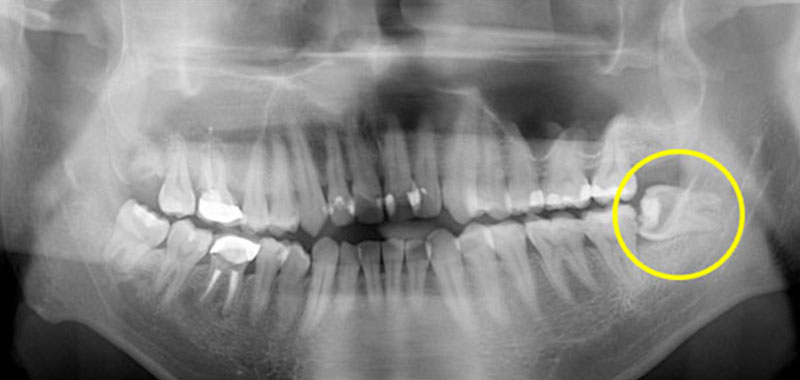

兩側下顎深埋在骨頭裡的水平智齒,右邊上顎智齒也深埋在骨頭內長不出來!這樣的智齒如果沒有症狀不一定要拔